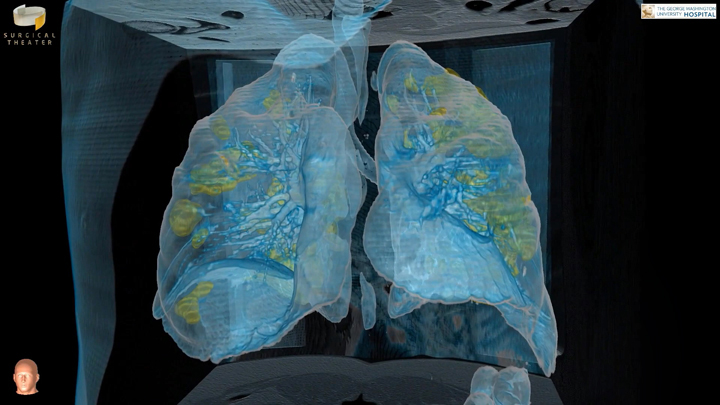

新冠病毒正在全球范围内爆发,但很多人对它不以为然,依然不愿意佩戴口罩,甚至外出聚集。患者通会出现轻度发烧和类似流感的症状,并可能随后出现呼吸能力迅速下降。但是,我们目前难以清晰地探索病毒是如何对人类肺部造成影响。日前,乔治华盛顿大学医院(George Washington University Hospital)发布了一个COVID-19病毒感染肺部的“虚拟现实”画面,并希望通过这样的方式来警醒民众。

所述VR视频是由胸外科主任基思·莫特曼(Keith Mortman)博士和VR成像软件开发商Surgical Theatre共同开发。他们利用了真实世界的数据来创建医疗级的3D可视化效果。

莫特曼曾利用Surgical Theatre的软件向术前患者展示其肺部或食道肿瘤,但在对受感染患者进行CT扫描后,他意识到可以利用这种方法来揭示COVID-19的严重性。

肺部通常为不透明,并会描绘为半透明的蓝色,而感染区域则用黄色表示。对于乔治华盛顿大学医院的可视化画面,除了病毒传播到整个肺部的原始影响之外,它同时显示出COVID-19病毒对人体的影响,如多个炎症区域的出现,肺活量大幅衰竭并足以迫使患者使用呼吸机进行住院治疗。莫特曼表示:“我们所看到的损害并不局限于肺部的单个部位。它会对整个双肺造成严重损害。”

一个特别令人担忧的发现是,如果炎症没有随着时间消退,COVID-19幸存者最终可能会受到严重的持久肺损伤。莫特曼解释说,“它基本上会在肺部形成疤痕,并且可能影响患者的长期呼吸能力。”

他希望通过3D可视化工具逼真地呈现疫情的严重性,并真正警醒使固执的公众,促使他们留在家里,洗手并采取其他预防措施,从而确保自己和社区的安全。